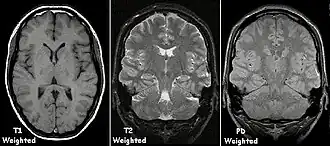

Magnetic resonance imaging (MRI) is a common form of biological data visualization used to form pictures of internal biological processes. Different settings of radiofrequency pulses and gradients result in different image appearances; these combinations are known as MRI sequences. A particularly notable subset of MRI is magnetic resonance angiography, which is a group of techniques used to image arteries and veins. MRI's imaging utility is further expanded upon by diffusion MRI and functional MRI, which can be used to capture neuronal tracts and blood flow respectively.

In general, two aspects of the relaxation process are measured: the time taken for the magnetic vector to return to its resting state (also known as T1 or spin–lattice relaxation), and the time taken for the axial spin of the hydrogen protons to return to its resting state (also known as T2 or spin–spin relaxation).[47] To create a T1-weighted image, the MR signal is measured by changing the amount of time between RF pulses (also known as the time to repeat, or TR). To create a T2-weighted image, the MR signal is measured by changing the amount of time between delivering the RF pulse and receiving the RF energy signals from the hydrogen protons (also known as the time to echo, or TE). The dominant signal intensities of T1 image weighting are fluid (black due to low intensity), muscle (grey due to intermediate signal intensity), and fat (white due to high signal intensity). Fat suppression is applied to many T1 weighted sequences to suppress the brightness of the signal created by it. The dominant signal intensities of T2 image weighting are fluid (white), muscle (grey), and fat (white). T2 signals are also often emphasized or suppressed depending on what the goal of the imaging is; notable examples include fat suppression, fluid attenuation, and susceptibility weighting.

Also of note are proton density (PD) weighted images, which are generated using a long TR and a short TE. PD is useful for differentiating between fluid, hyaline cartilage and fibrocartilage, which makes it ideal for imaging joints. Outside of joint imaging it has largely been replaced by fluid attenuated inversion recovery (FLAIR), an inversion recovery sequence that removes the signal from cerebrospinal fluid.[48]